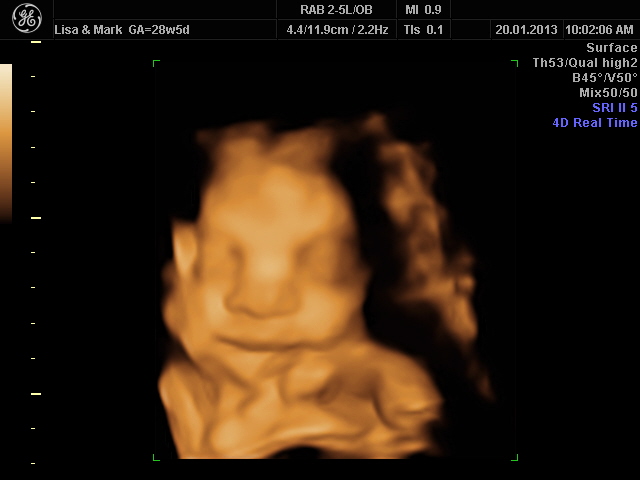

Week 28 Scan Posted on January 20, 2013 by admin Posted in Scan 1 Comment On Sunday 20th January we returned to Peek-A-Baby to see the second 4 dimensional scan using the sonography to visualise the ghostly 2D ultrasound images.